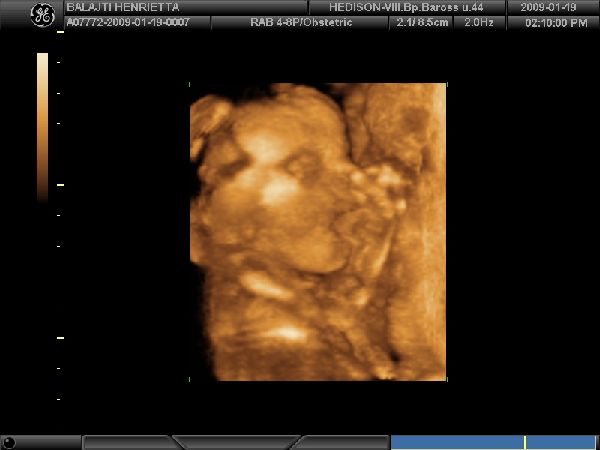

Egy kis mosoly

Egy kis mosoly  Hammm Bekapom

Hammm Bekapom  A kis Hercegnő!!!

A kis Hercegnő!!!

Kis Gyönyörűség

Kis Gyönyörűség  És Apája orra az én orrom

És Apája orra az én orrom